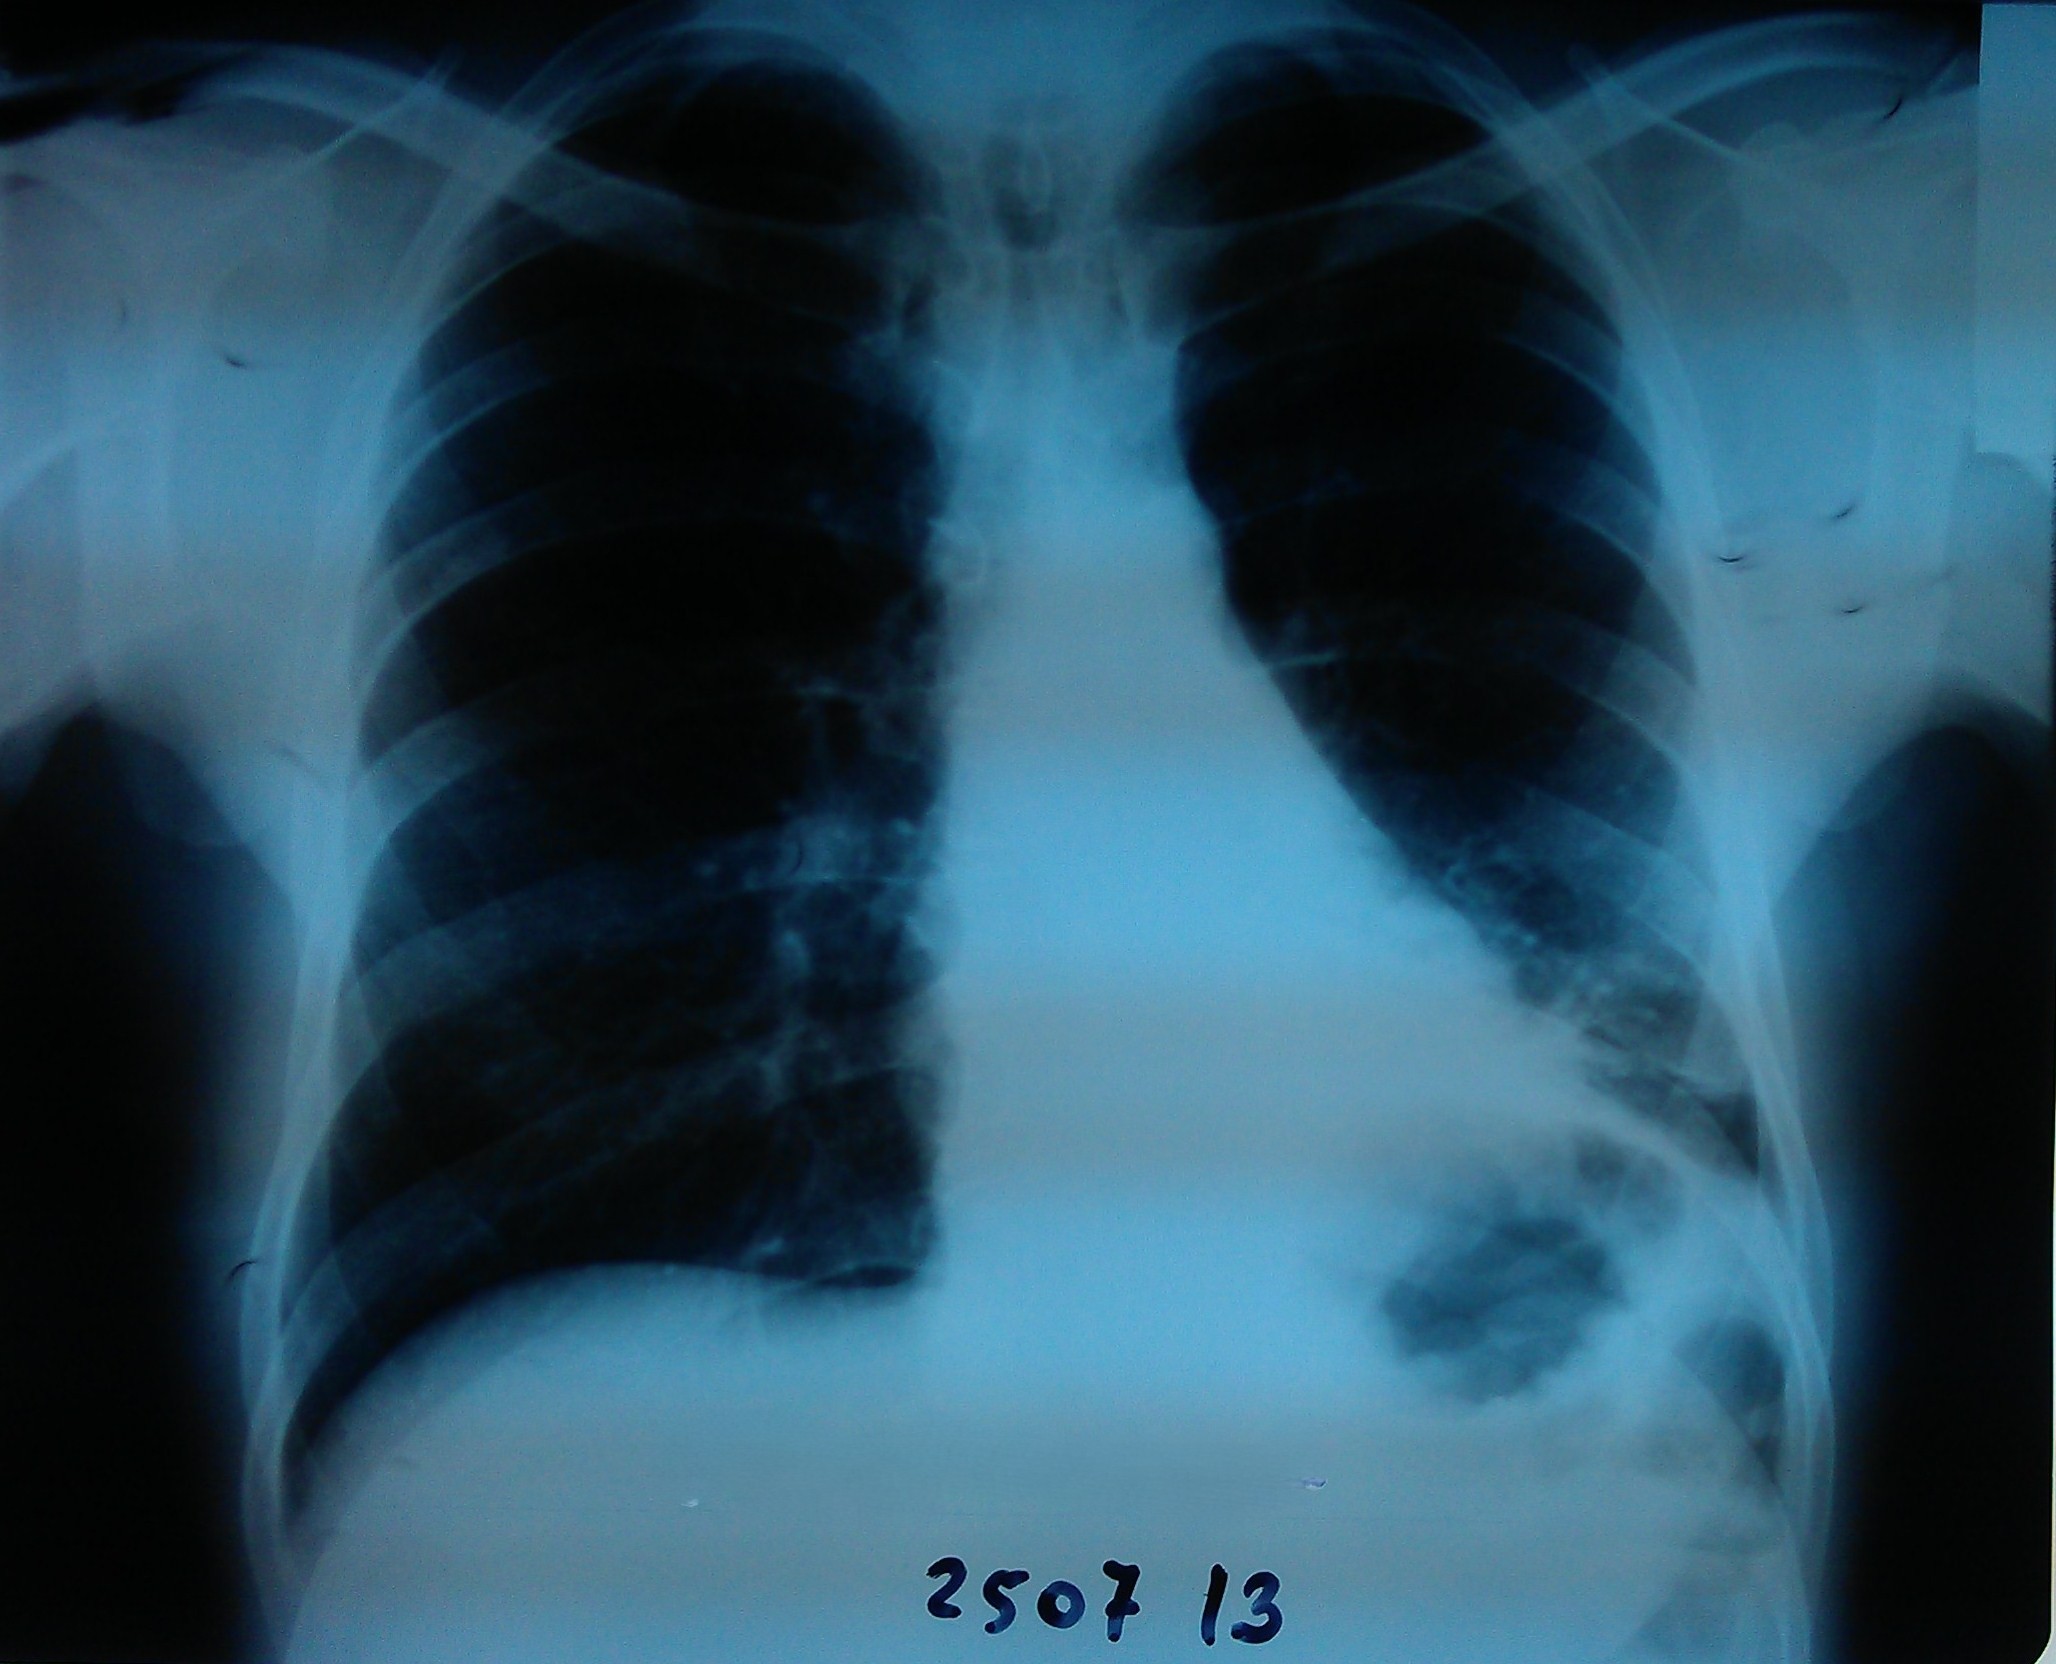

- გულმკერდის რენტგენოგრაფია სტენტირებიდან 4 დღეში

მარცხენა ფილტვი ნაწილობრივ გაშლილია.